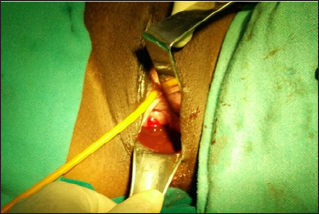

The mass appeared to be arising from anterior vaginal wall. A provisional diagnosis of anterior vaginal wall cyst was made and imaging studies performed. The ultrasound was suggestive of retention cyst (Figure 2). CT scan too pointed towards retention vaginal cyst (Figure 3). Since the diagnosis was not clear; the case was taken up for detailed examination under anesthesia, the mass was occupying the whole of vagina hence one could not go beyond the mass to locate the cervix, detailed per speculum examination under anesthesia revealed a small discolored spot (Figure 4) which when probed exuded tarry material (Figure 5). A diagnosis of cervical stenosis with retained blood was made and cervical opening was dilated to allow the collected blood to drain out. Appx 700 ml (Figure 6) of dark chocolate material was removed and cervix attained almost normal appearance and now the uterus could be palpated distinctly which appeared of normal size and shape. The lump abdomen had disappeared.

Figure 5: Chocolate material being drained.